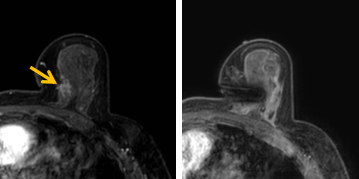

患者李女士磁共振檢查發(fā)現(xiàn)右乳內(nèi)側(cè)高度可疑病變,病變小摸不到,超聲和X線攝影(鉬靶)都看不到,怎么辦?要想明確病變性質(zhì),必須進(jìn)行磁共振引導(dǎo)下精準(zhǔn)足量的活檢,但是這種技術(shù)操作難度大、軟硬件要求高。

經(jīng)過仔細(xì)查體并分析所有影像資料,陳寶瑩發(fā)現(xiàn),病變靠近胸大肌,容易造成術(shù)中損傷?;颊呷榉枯^小,病變在內(nèi)側(cè),導(dǎo)致乳房不易固定,進(jìn)針難度大,與患者充分溝通后,陳寶瑩帶領(lǐng)團隊,制定了細(xì)致的操作方案,術(shù)中,醫(yī)護團隊反復(fù)調(diào)整體位和固定架的角度及方向,利用隔離技術(shù)保護好周圍組織。受乳房形態(tài)和病變位置的限制,醫(yī)生只能蹲著、跪著進(jìn)行操作,經(jīng)過30多分鐘終于順利完成,精準(zhǔn)獲取了足量的組織,而且一針到位,創(chuàng)傷小、出血少,患者沒有任何不適,做完即回家休息。幾天后,病理證實是一種特殊類型的早期乳腺癌,為后續(xù)進(jìn)一步治療方案的制訂提供了準(zhǔn)確依據(jù)。